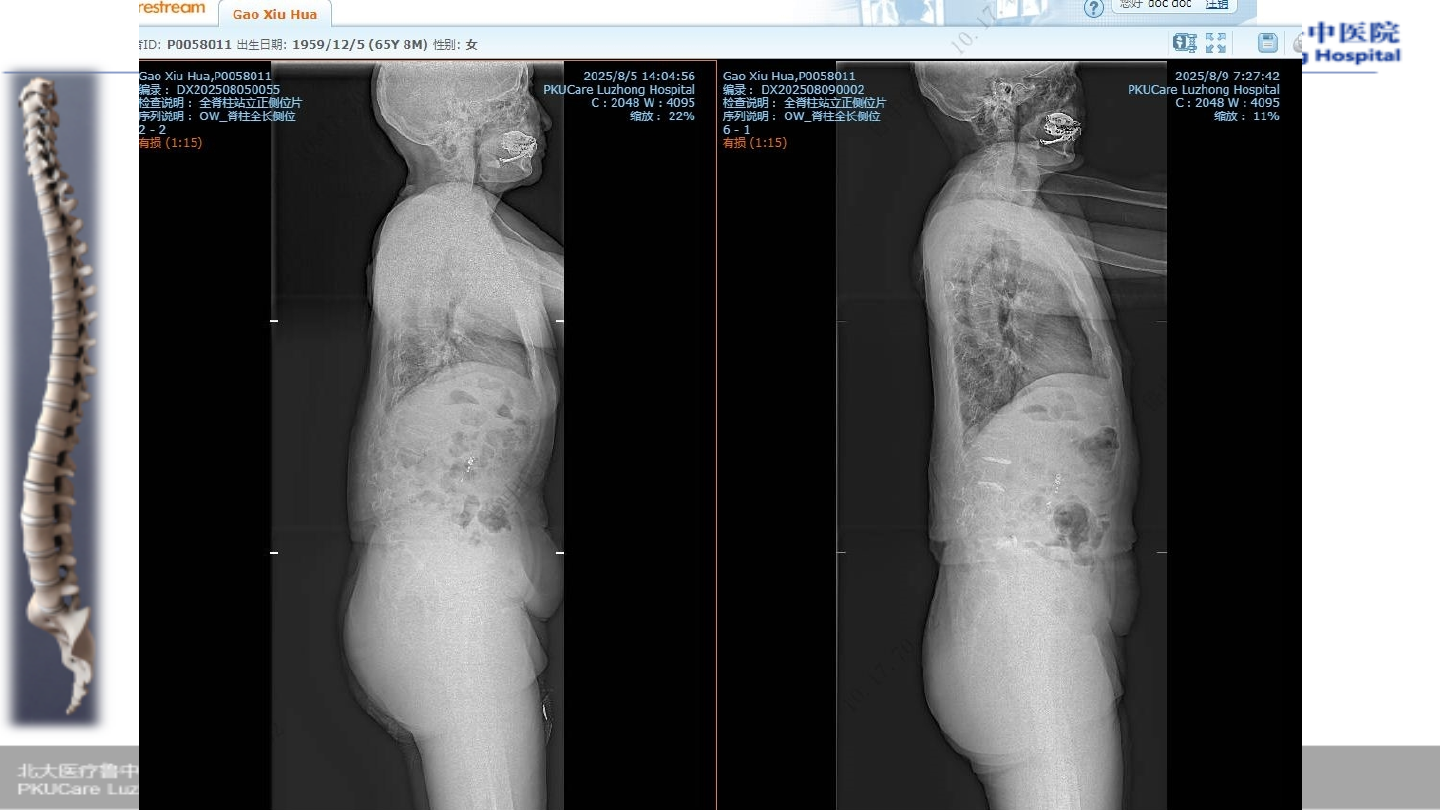

u

患者:高某,女性,

65

主诉:

腰疼伴行走困难,双下肢麻木

1

症状:腰部疼痛,双下肢行走困难,双下

肢小腿外侧疼痛麻木

.

Oswestry

功能障碍指数(

ODI

):

85%

VAS:8

病例

2

术前腰椎

X-ray